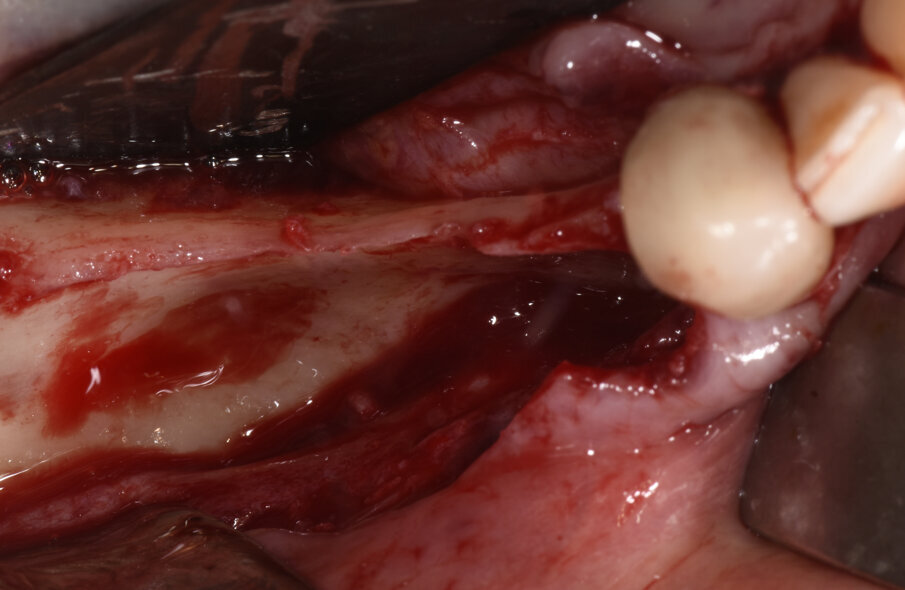

Dopo un’adeguata preparazione parodontale mediante igiene orale professionale eseguita 7 giorni pri - ma dell’intervento, una profilassi antibiotica con Amoxicillina e acido clavulanico (2 g un’ora prima dell’intervento), una profilassi antisettica con clorexidina 0,12% collutorio e una profilassi antiedemigena con bromelina da 3 giorni prima dell’intervento, la paziente è stata sottopo - sta alla prima fase chirurgica in anestesia locale. L’accesso alla zona da ricostruire è stato eseguito mediante un lembo muco-periosteo in cresta con scarico mesiale su 4.2 e distale in zona retromolare (Fig. 3). Sono stati eseguiti adeguati rilasci periostali in modo da rendere priva di tensione ed ermetica la successiva sutura del lembo e in modo da minimizzare l’e - matoma post-operatorio. Nella zona del forame mentoniero, i rilasci sono stati eseguiti tramite dissezione e identificazione per via smussa dei rami del nervo mentoniero. Il prelievo di osso autologo particolato è stato prelevato dal ramo mandibolare, distalmente alla zona da ricostruire minimizzando i disagi post-operatori, mediante uno scraper (SafeScraper Twist®). La griglia è stata provata vuota nel sito ricevente per verificarne la congruità e ogni residuo di tessuto connettivo è stato rimosso in modo da consentire un adeguato attecchimento. Per aumentare la rivascolarizzazione precoce del materiale innestato, sono state eseguite perforazioni multiple della corticale ossea del sito ricevente mediante fresa a rosetta molto piccola. Dopo riempimento della griglia con un mix di osso autologo ed eterologo (Bio-Oss® - Gestlich Biomaterials, Wolhusen, Svizzera) in rapporto 1:1, la stessa è stata fissata con 2 micro-viti in titanio di 1.4 mm di diametro (MCBio, Lomazzo, Como, Italia) ed è stata ricoperta con una membrana riassorbibile in collagene suino (Biogide® - Gestlich Biomaterials, Wolhusen, Svizzera) (Figg. 4a, 4b). La sutura, per prima intenzione e priva di tensioni, ha previsto un’alternanza di punti a materassaio orizzontale con punti singoli in acido polilattico-poliglicolico riassorbibile (Vycril® 5/0) (Fig. 5).

Fig. 3_Visione intra-operatoria dopo l’allestimento di un lembo a tutto spessore che evidenzia il difetto osseo.